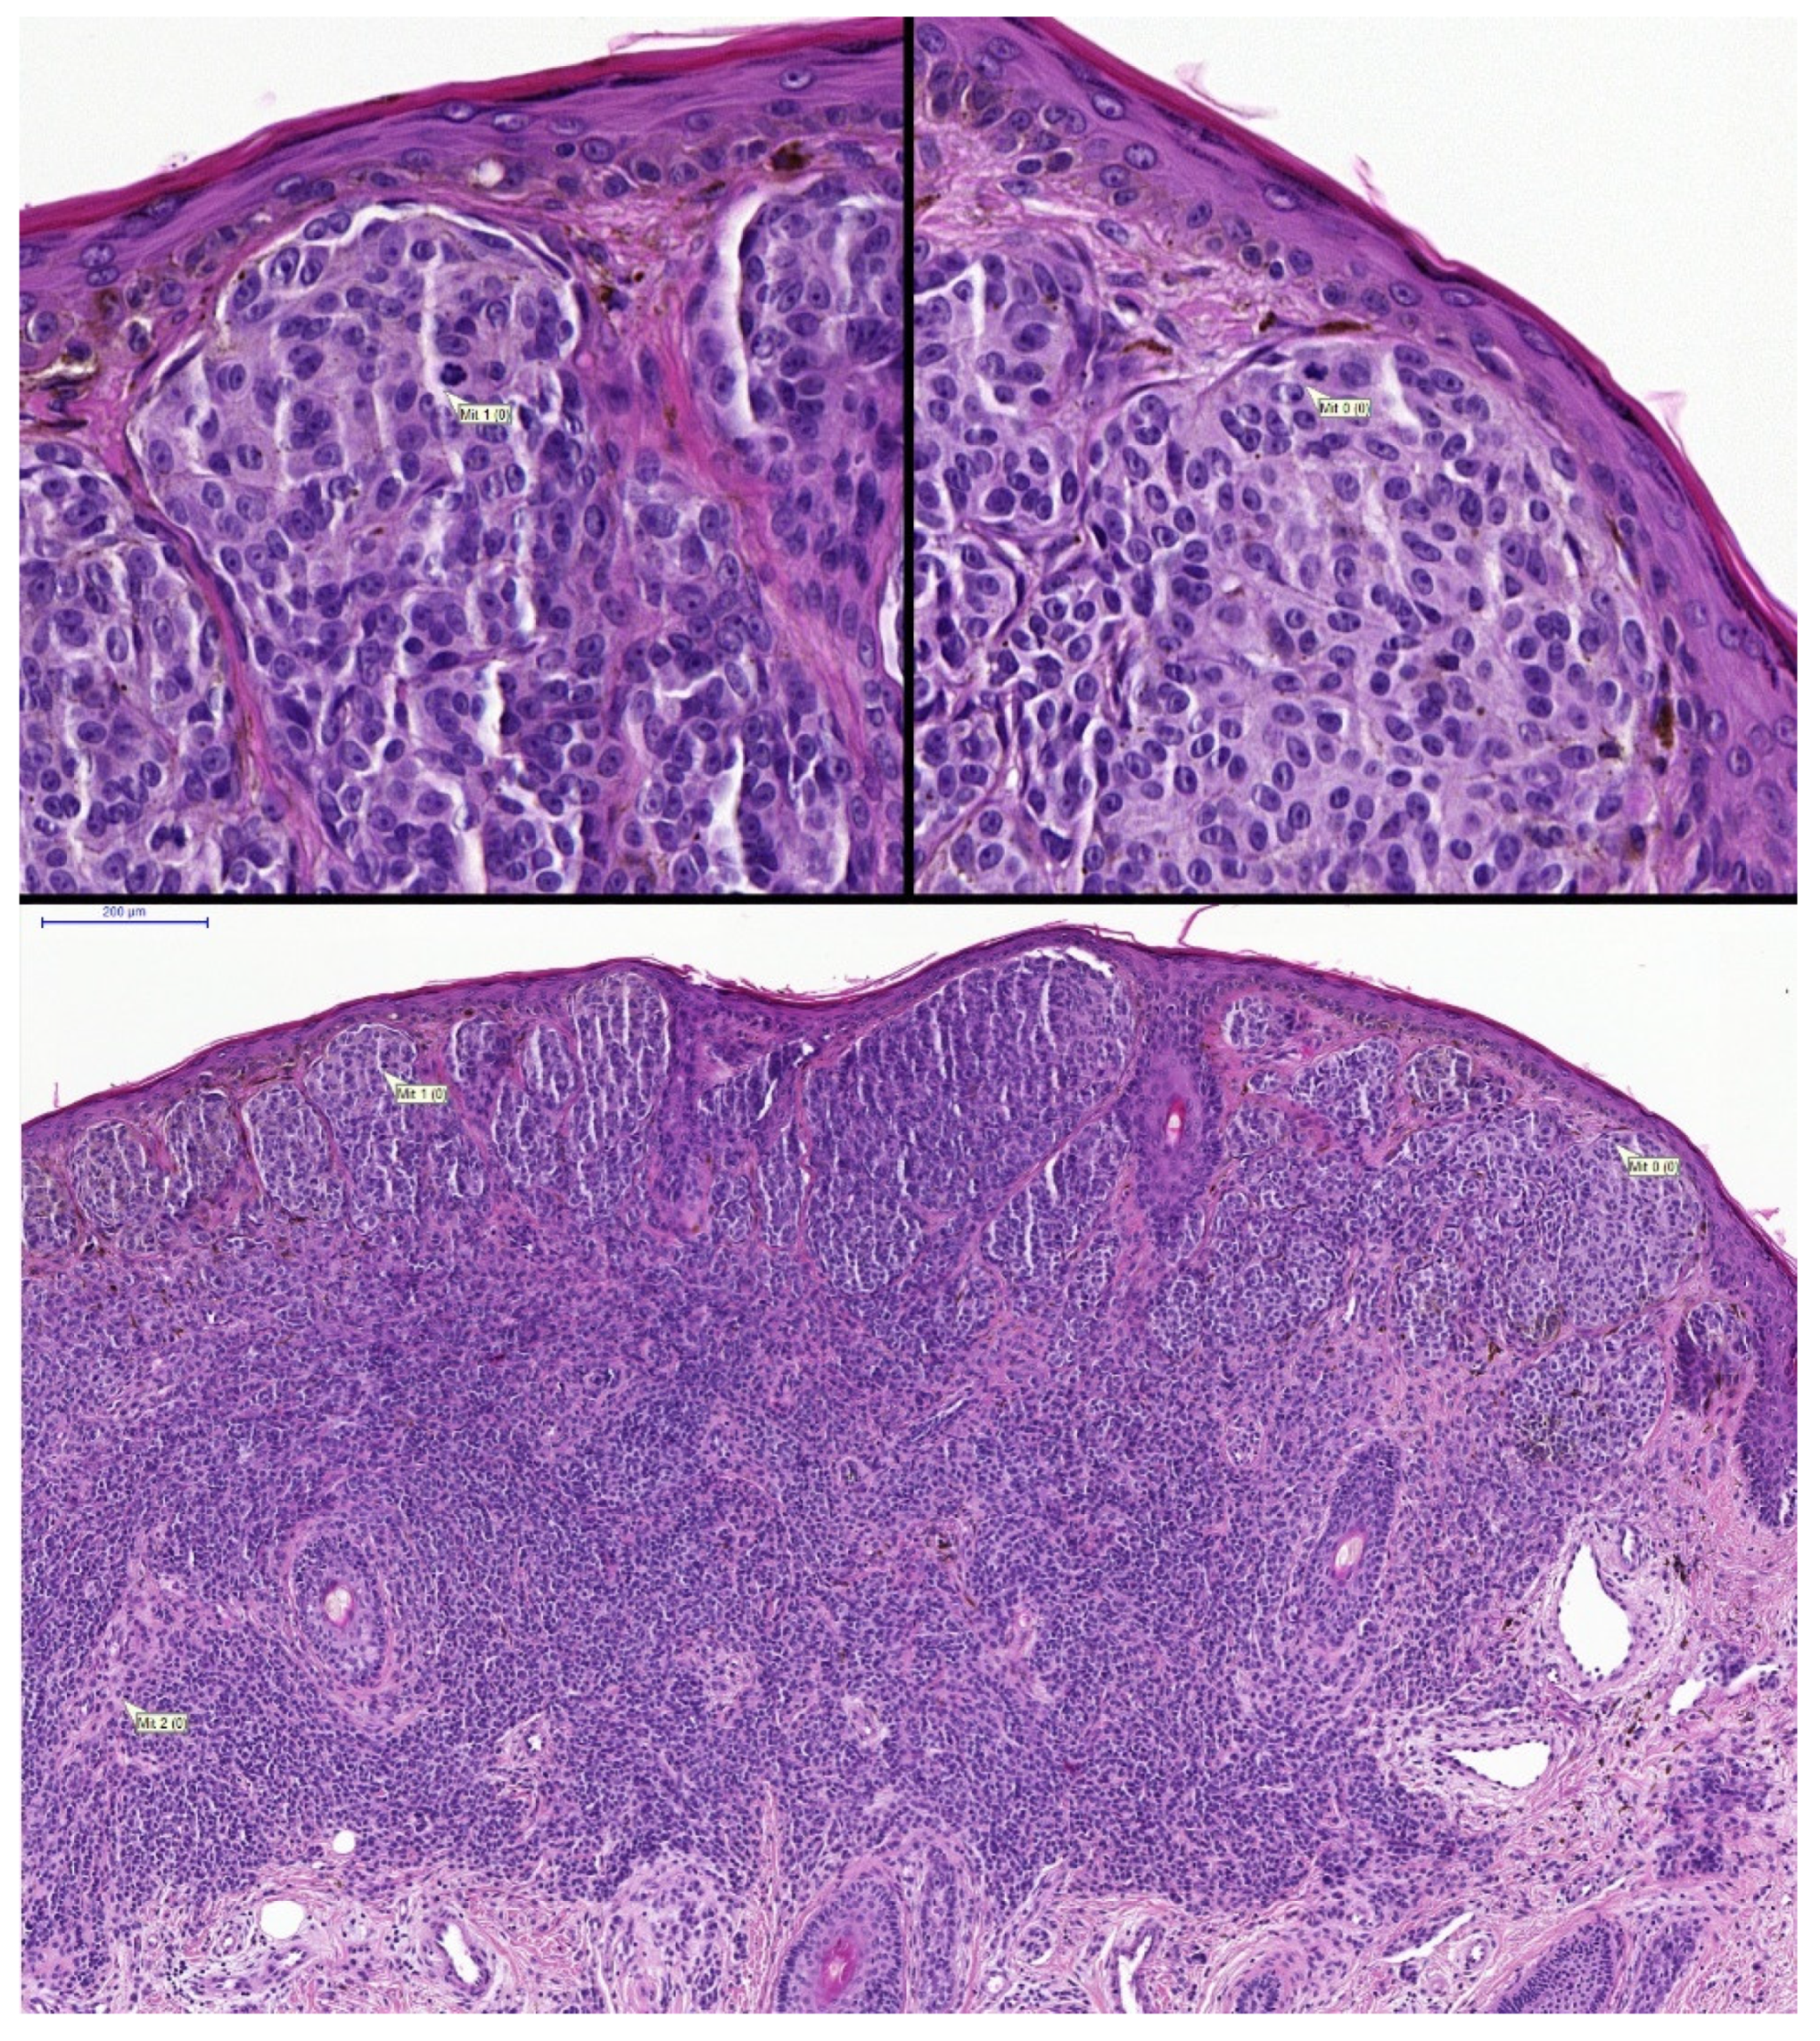

- Sturm, B.; Creytens, D.; Cook, M.G.; Smits, J.; van Dijk, M.; Eijken, E.; Kurpershoek, E.; Kusters-Vandevelde, H.V.N.; Ooms, A.; Wauters, C.; et al. Validation of Whole-slide Digitally Imaged Melanocytic Lesions: Does Z-Stack Scanning Improve Diagnostic Accuracy? J. Pathol. Inf. 2019, 10, 6. [Google Scholar] [CrossRef]